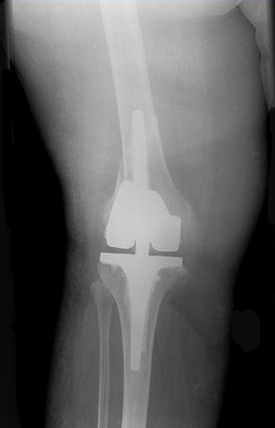

Rorabeck II

A Rorabeck Type II Fracture is a displaced fracture and the prosthesis is intact. Literature indicates that a ORIF is recommended [1].